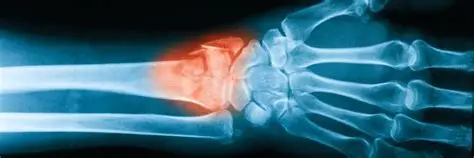

Galeazzi Fracture

Smith Fracture

Carpal Tunnel Syndrome

Wrist Fractures